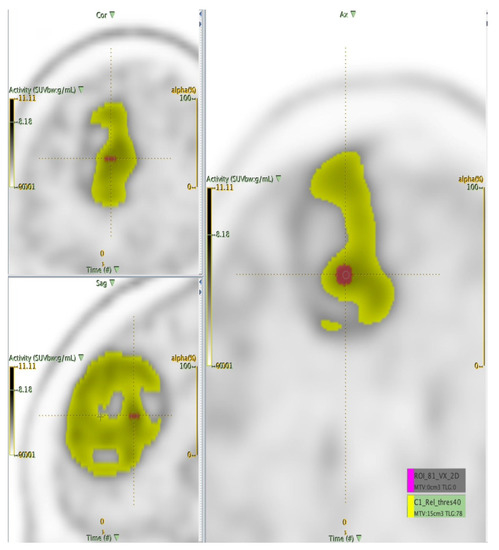

2.2.1. The Target Segmentation

2.2.2. Extraction of the Radiomics Features